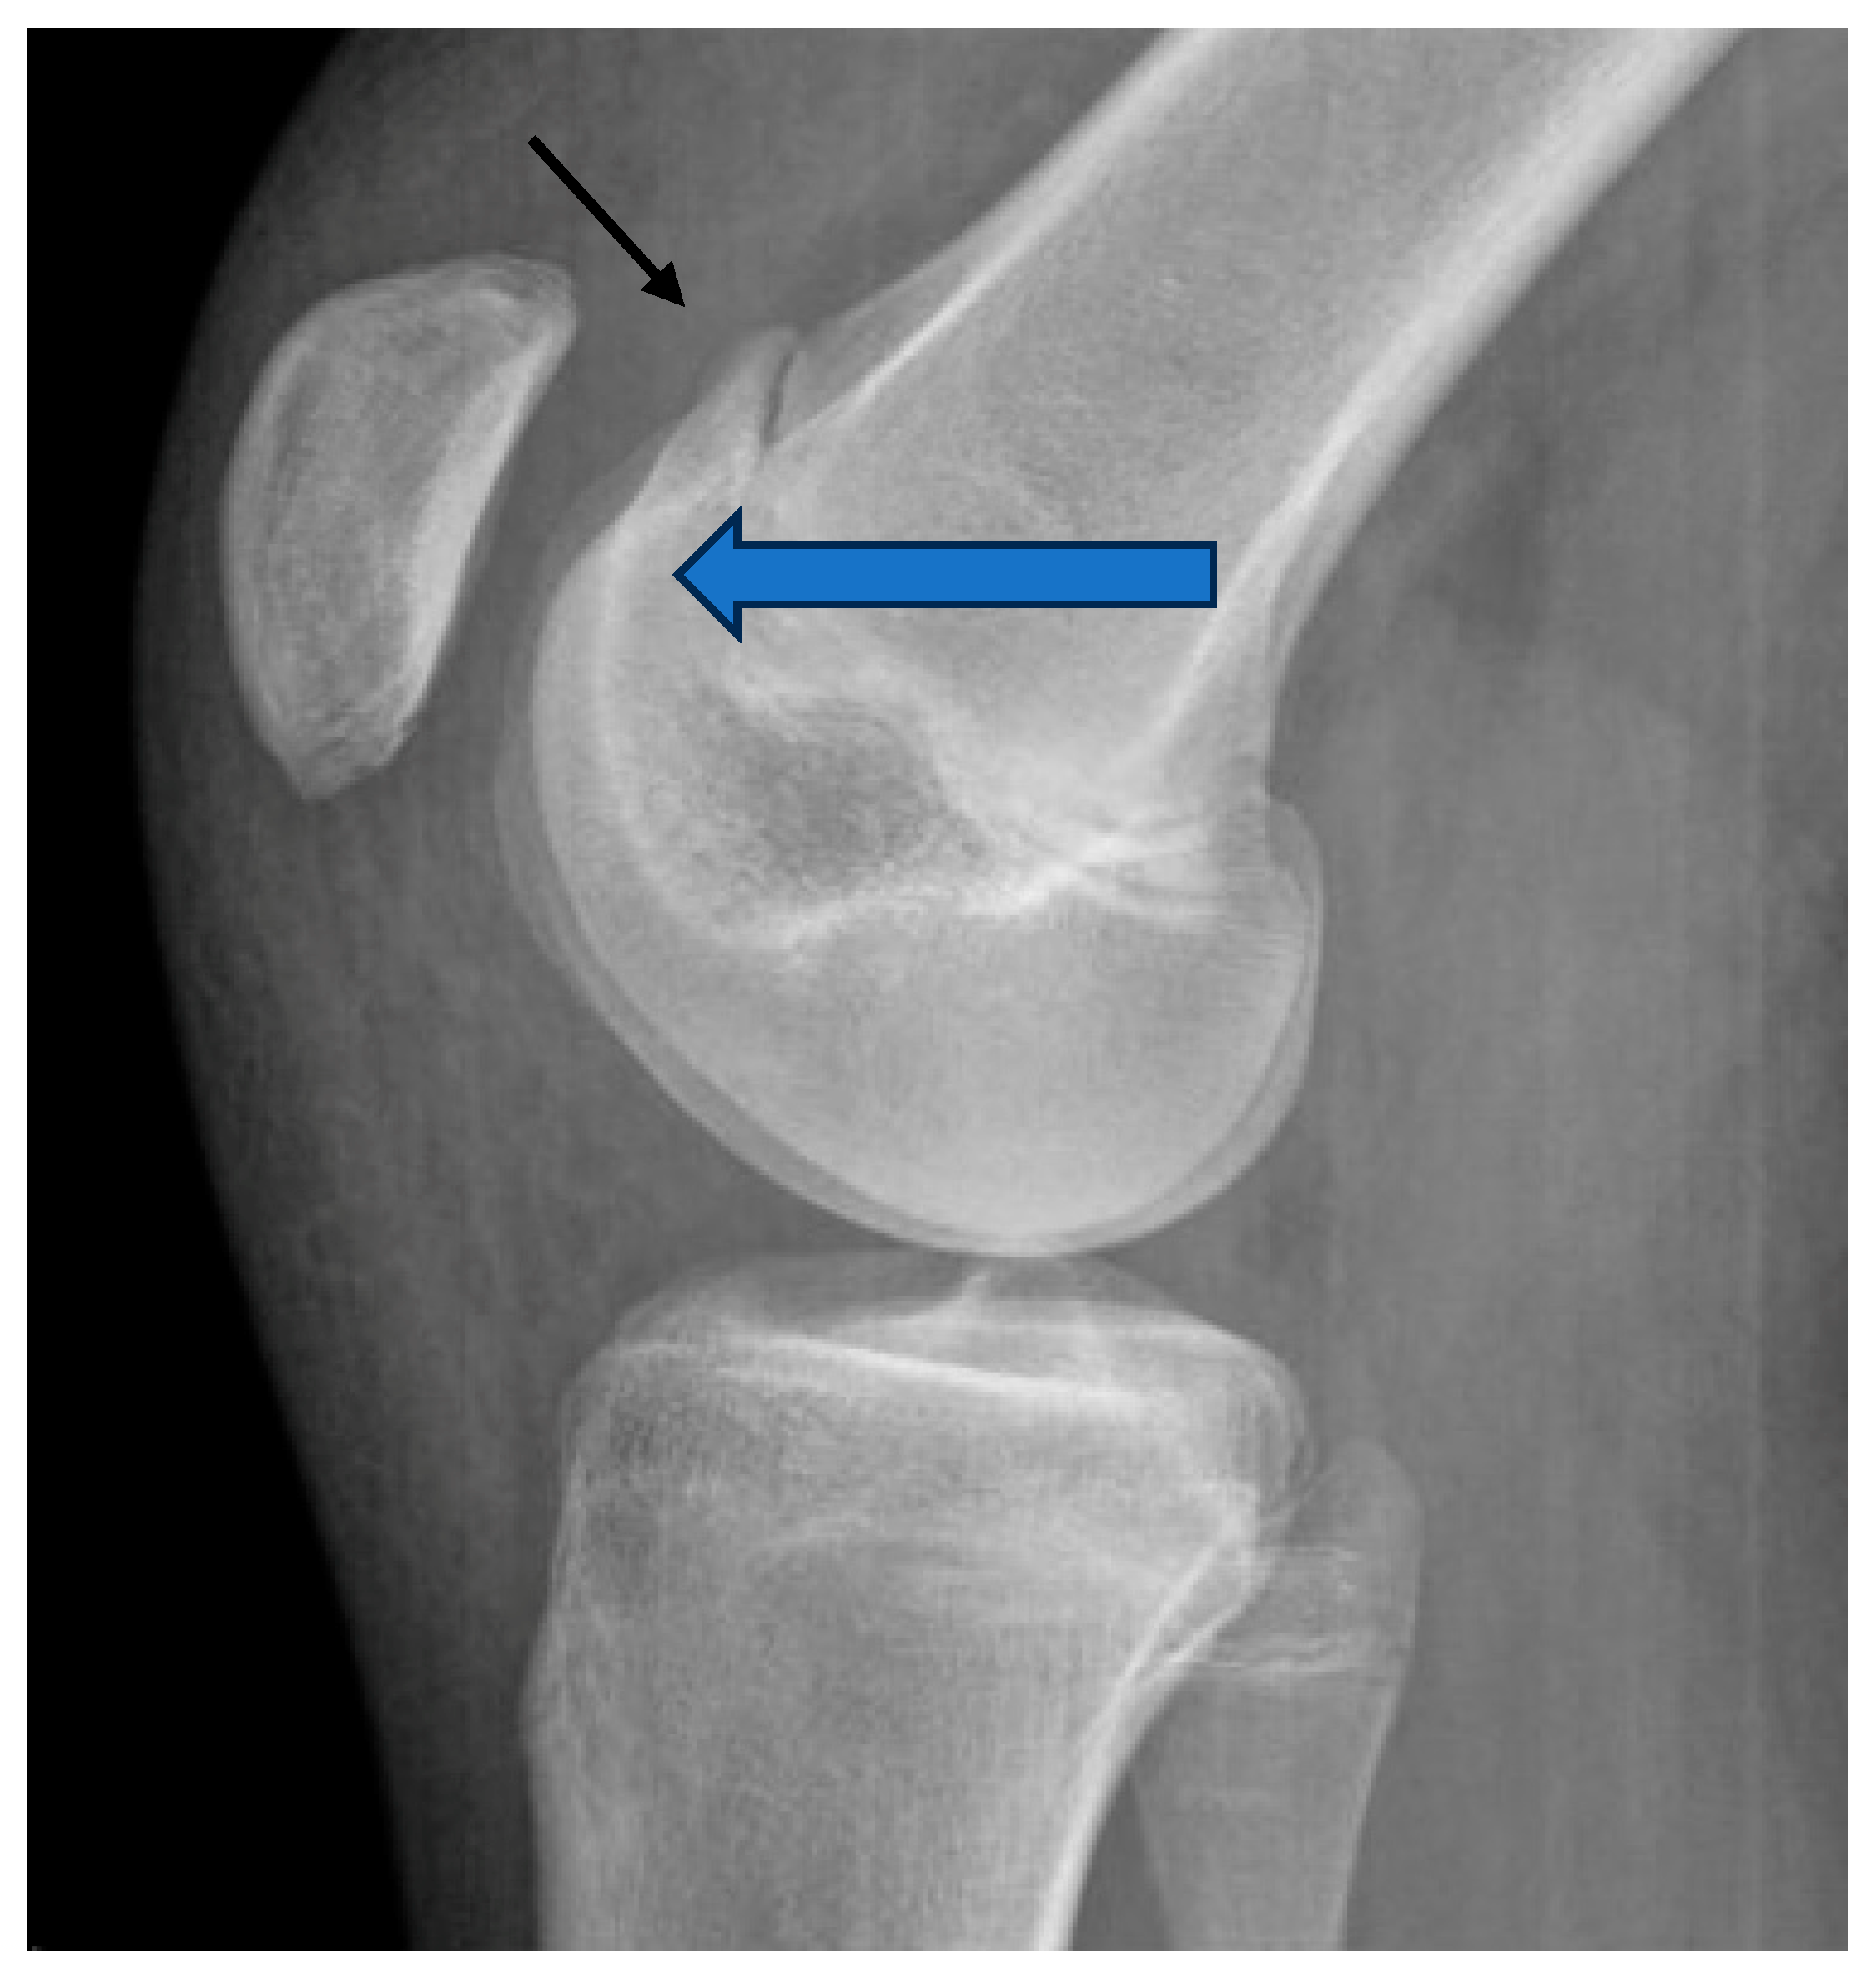

3.3. Trochlear Dysplasia

8.3. Trochlear Dysplasia